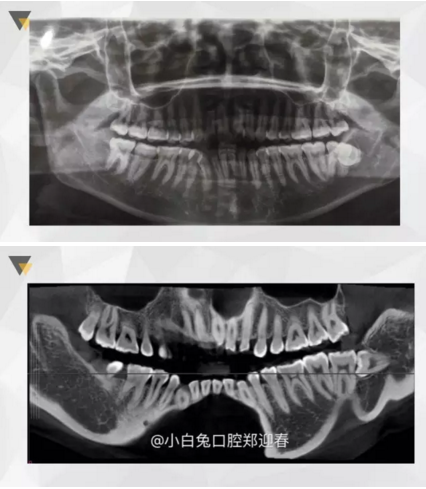

阻生齒外科聯(lián)合正畸治療

24.png

25.png

26.png

27.png

28.png

來(lái)源:小白兔口腔鄭穎春